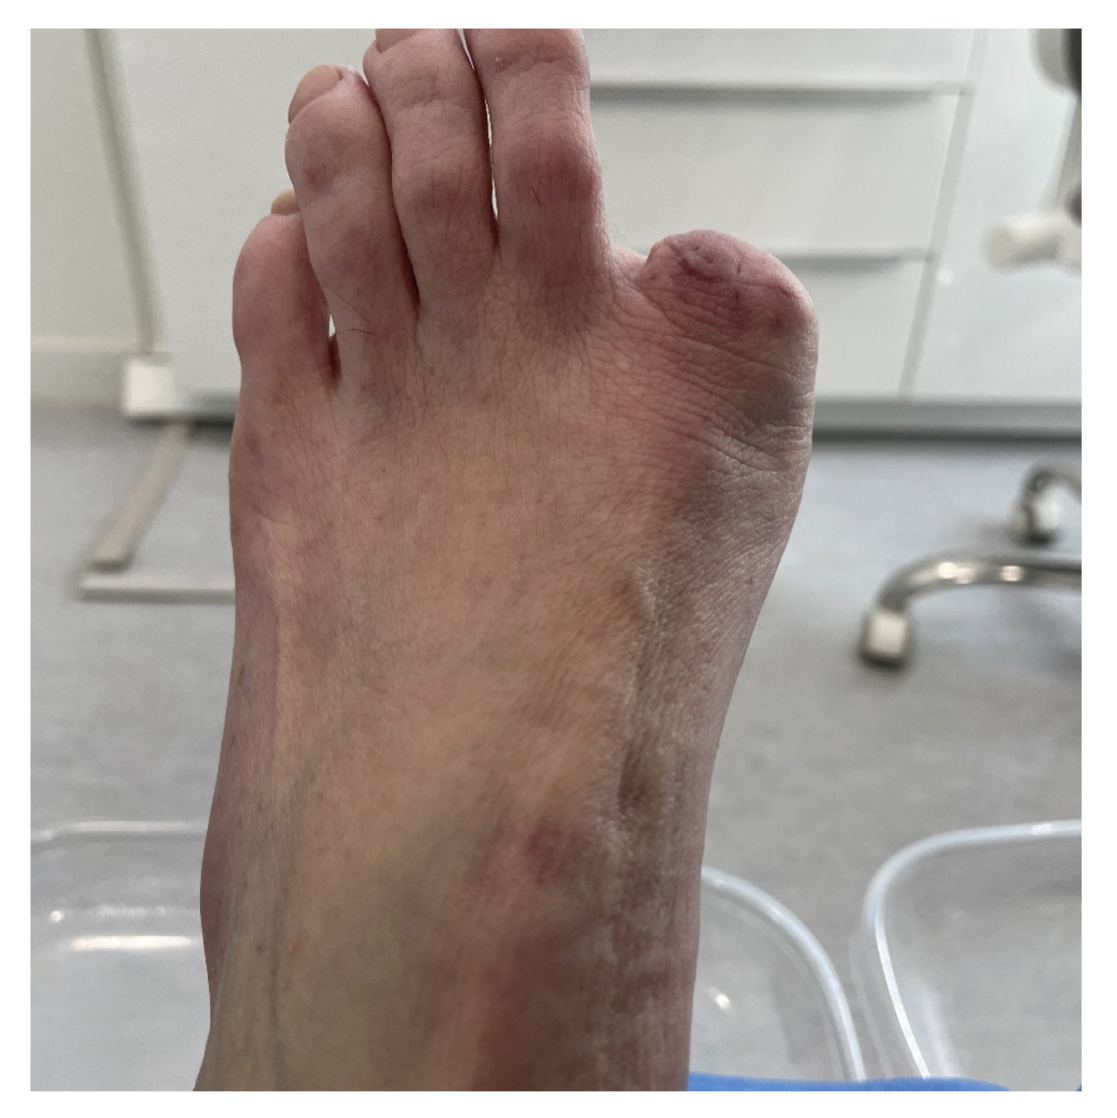

La paciente refiere proceso de inicial de onicocriptosis de 7 meses de evolución (septiembre de 2022), en el borde medial del primer dedo del pie izquierdo, con la presencia de tejido de granulación ungueal en dicho borde, el cual le produce dolor e inflamación digital (Figura 1). La paciente recibe tratamiento por su podólogo que consiste en quiropodia y limpieza del canal; se pautan posteriormente curas diarias con mupirocina para la lesión. Existe mala evolución de la lesión en los días siguientes con aumento de dolor y sensibilidad al tacto. Se modifica el tratamiento pautando amoxicilina/ácido clavulánico 875/125 mg, 1/8 h junto con el uso de analgésicos orales (Figura 2). La paciente continúa con mala evolución sintomatológica y acude a su centro de salud donde se realiza radiografía con la cual se descarta la presencia de infección profunda (osteomielitis).

Figura 1. Proceso inicial de onicocriptosis y granuloma reactivo.